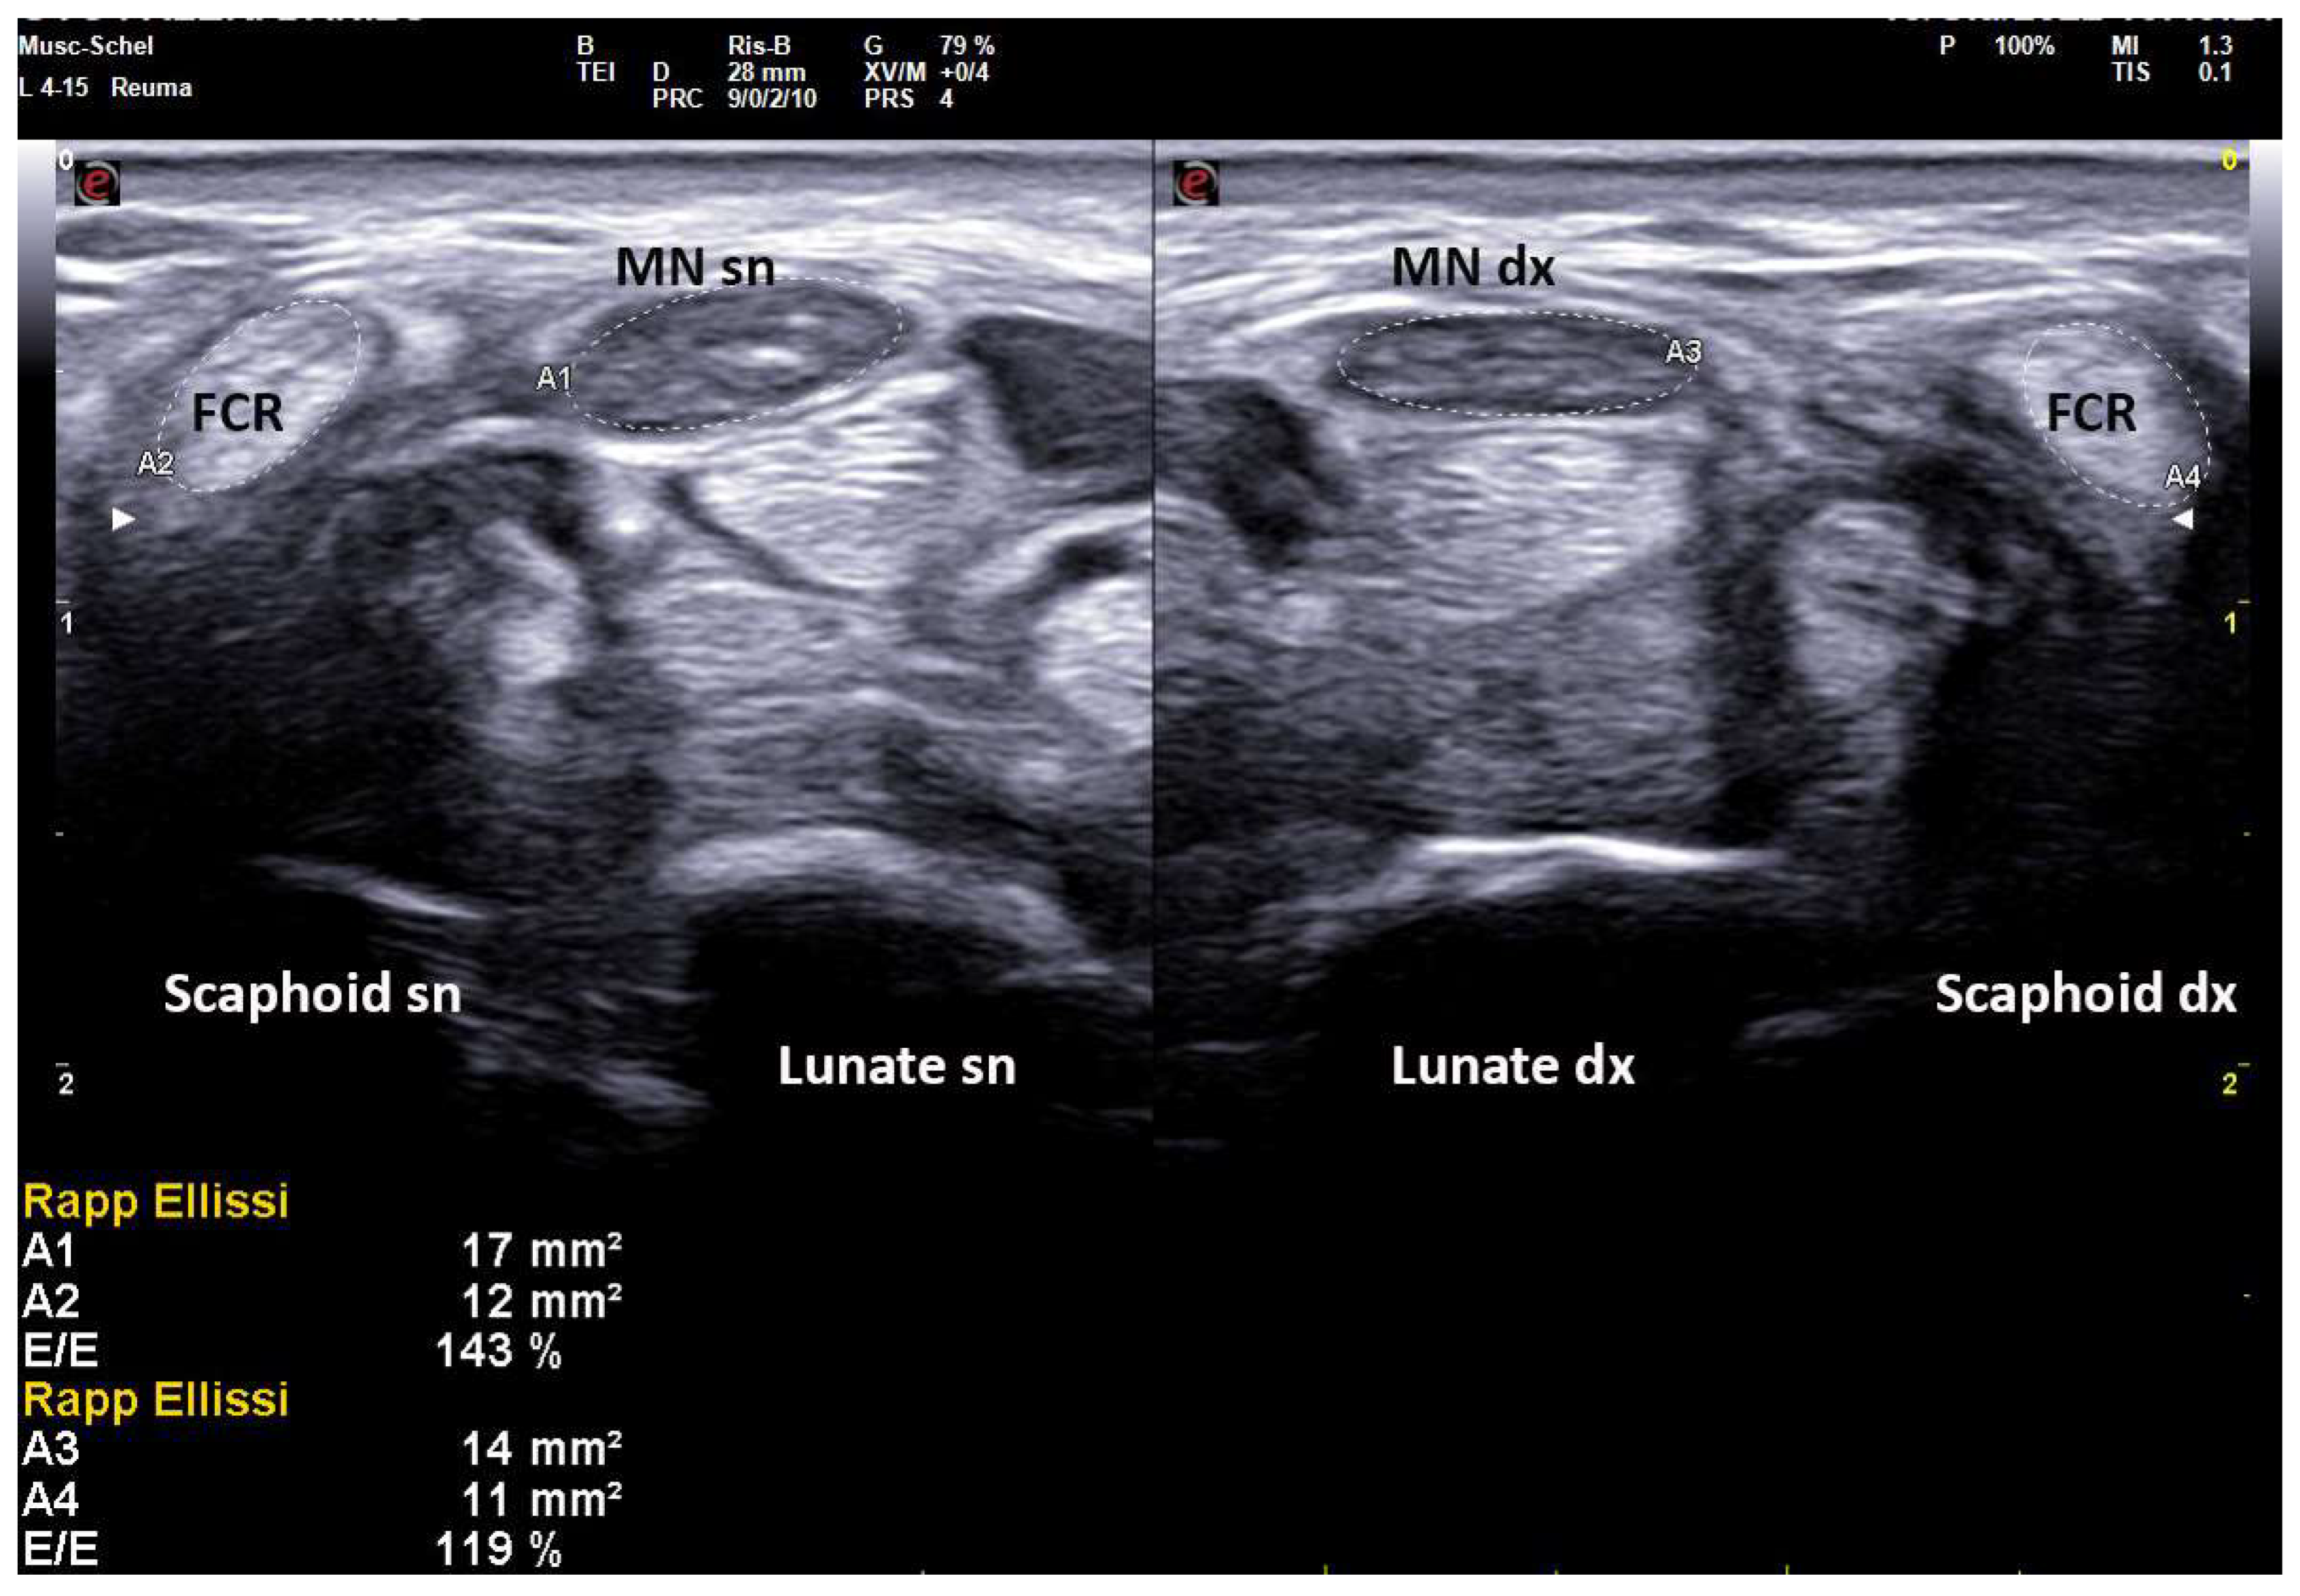

In fact, an earlier study showed a positive correlation between CSA and wrist circumference, height and weight [5]. For these reasons, smaller people have lesser wrist circumference and lesser CSA of the median nerve also in pathologic conditions. On the other hand, taller subjects can have MN-CSA over cut-off in the absence of compressive neuropathy (Figure 1) [16].

Figure 1. Transverse scan over left carpal tunnel of a tall male, asymptomatic for CTS in left hand (180 cm × 85 kg, 19 cm of wrist circumference). Linear 6–18 MHz probe. The MN-CSA (area 1) results of 11 mm2 are suggestive of pathologic swelling, but EDS was normal (PS = 0, performed as control side, for CTS in the right side). The flexor carpi radialis (FCR) shows a CSA (area 2) of 14 mm2. MN = median nerve, FPL = flexor pollicis longus, * = transverse ligament, FDS = flexor digitorum superficialis.